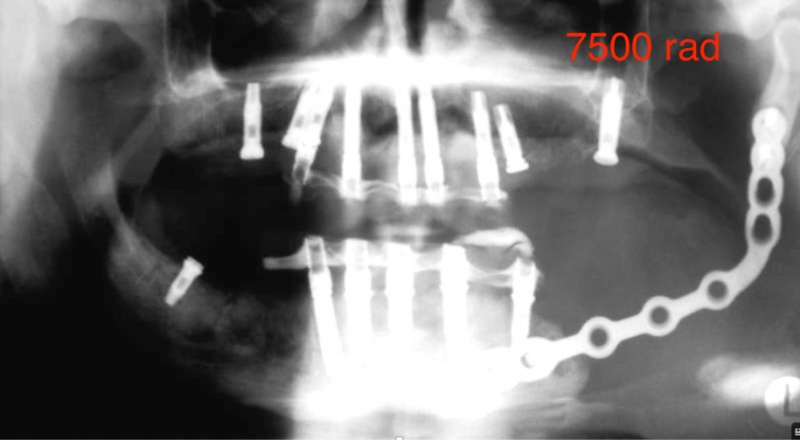

Is het mogelijk om implantaten te plaatsen bij patiënten die bestraald zijn geweest in de mondregio?

Absoluut! Dr. Defrancq zet zich graag in voor deze patiënten die bestraald zijn geweest voor een mondtumor.Het is een prachtige indicatie, omdat vele patiënten extreem pijnlijke en gevoelige tanden heeft na bestraling. Deze ingreep betekent ontzettend veel voor hen, niet alleen op functioneel vlak maar ook op vlak van comfort en zelfwaarde.

Een zorgvuldige werkwijze is noodzakelijk om de tanden zo atraumatisch mogelijk te verwijderen. Dr. Defrancq heeft dergelijke constructies bij een tiental patiënten uitgevoerd zonder noemenswaardige moeilijkheden en met immediate loading. Vaak wordt een uitvoering in porselein verkozen. Deze patiënten hebben immers vaak een heel droge mond hebben en onder deze omstandigheden voelt porselein veel comfortabeler aan dan hunsthars.